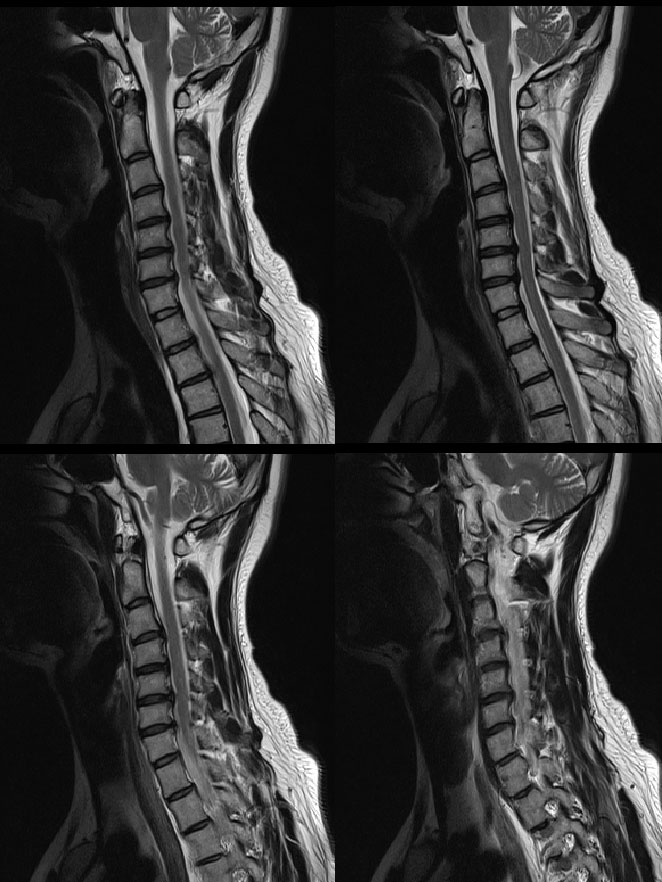

Ű 165 64 33 ڸǥغ ǥغ ϱ ȣϽ 1C.Ż, 1C., 6C.ڸ 6C.ھ Ḳ ()ũ( ߰Ż) ũ(߰Ż)ġ, 2009 4 ڰ ߰ ϰ MRI 3 4 5 Ż ̶ ũ ҽϴ. ڸǥغ ǥغ ϰ ߴ ġ 5 ܰ ȰġḦ ް MRI ٽ µ ´ ʰ ֽϴ. µ ϰ Ӹ ̰ ϴ ֽϴ. ============================================================= Խûϼ̰:ֹȣ 20091023093417skylove**** 迵 Ͽ ûϼ̽ϴ. ȭ ȣ* ȭ ϰ ־ٰ մϴ. Ϸ ǻ ϴ ̴ ǻ۾ڼ IJ ص帮. **Բ 帮 Դϴ. ** mri Ǵϰǵ ȣ Դϴ. 5 ġῡ ʾҴٸ ġᰡ ߸Ǿٱ ٴ Ͻô ħ ߸ Դϴ. ٸ ߿ ϳ ƮĪ ڼ ߸ Դϴ. ȣϽ ̶ mriκ Դϴ. ġ Ͽ ǥغ ȣ Ǵ üغñ ٶϴ. |